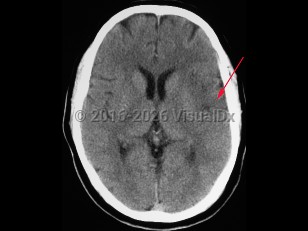

- Intracerebral hemorrhage – Bleeding directly into the brain parenchyma secondary to hypertension, trauma, bleeding disorders, aneurysm rupture, illicit drug use, or vascular malformations. Patients typically present with the gradual onset of symptoms over hours to days with headache, nausea, vomiting, and altered levels of consciousness. If the source of the hemorrhage is from the low-pressure side of the circulation, then the onset of symptoms is more likely to be gradual than if the source is from the high-pressure, arterial side, where symptoms can be quite abrupt in onset. Patients can also present with seizure.